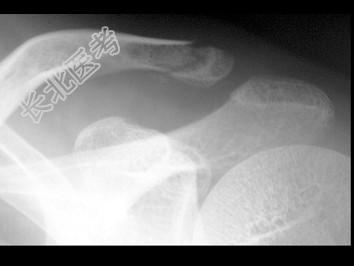

- 单项选择题男,25岁, 外伤后摄片,结合图像, 最可能的诊断是 ( )

A、肋骨骨折

B、锁骨骨折

C、原发性气胸

D、肋骨骨折伴气胸

E、锁骨骨折伴气胸